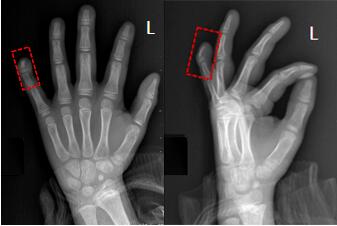

3.多指:橈側(cè)多指(復(fù)雜拇指畸形);尺骨側(cè)多指(小指多指);中指;(4)復(fù)雜性(以上兩者之一同時存在)。